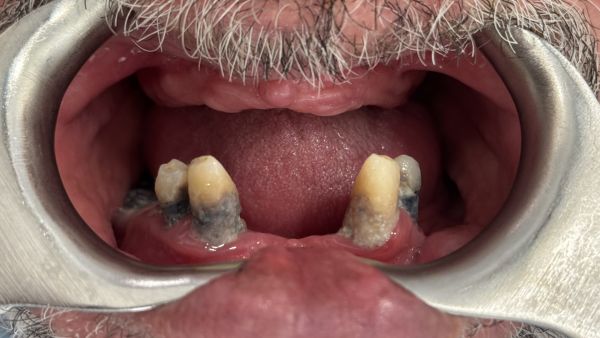

Implantes y Dientes Fijos en 24 horas